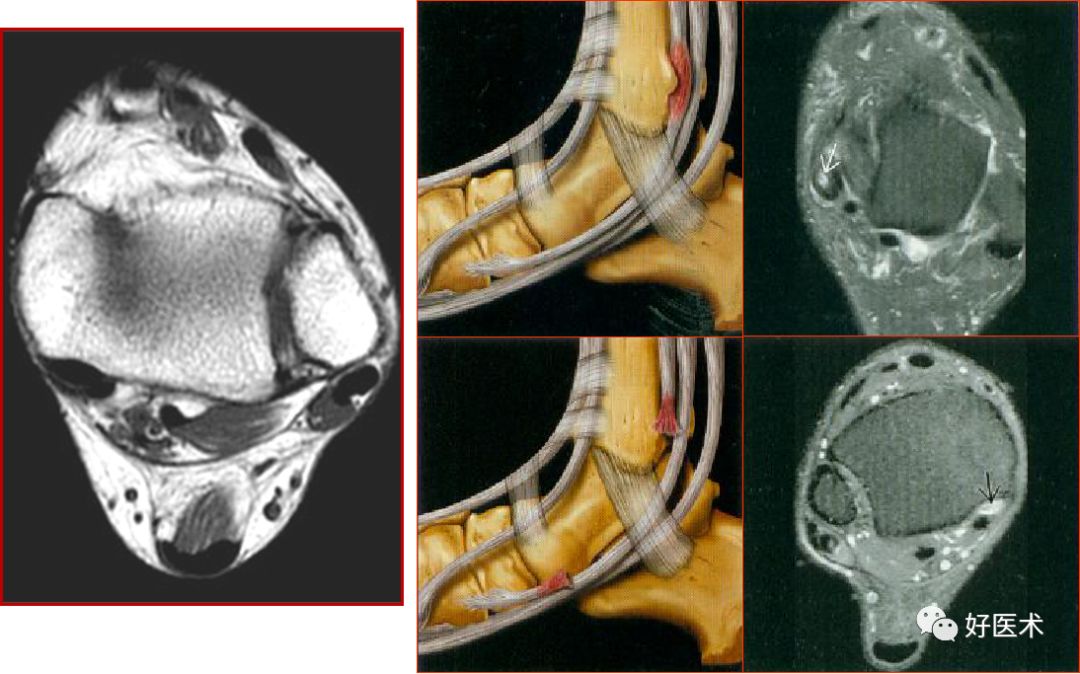

距腓前韧带

距腓前韧带撕裂

距腓后韧带

距腓后韧带部分撕裂

跟腓韧带

跟腓韧带急性完全撕裂